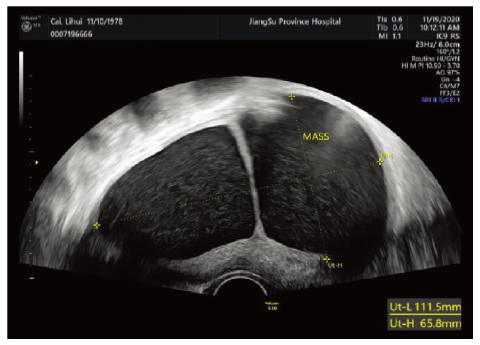

患者 女,42岁,因发现盆腔囊肿1年半,于2020年11月18日收治我院妇科。患者平素月经规律,无痛经。孕4产1,2002年足月剖宫产娩一健康男婴,3次流产均为社会因素在妊娠40 d左右药物流产或人工流产,具体年份不详。2019年5月在外院体检发现盆腔囊肿,大小不详。2019年9月15日就诊于我院妇科门诊,盆腔B超示:子宫右前壁见9.2 cm×6 cm×7 cm囊性包块,凸向浆膜下。建议手术治疗,患者拒绝。2020年9月20日患者于我院妇科门诊复诊,B超示(见图1):子宫右前壁见11.2 cm×6.6 cm×7.1 mm囊性暗区,向外突出,内见分隔及细密点絮状回声,分隔上探及少许血流信号。再次建议患者手术治疗,因工作原因,患者推迟至2020年11月18日入院治疗。

图1

子宫间皮囊肿的术前诊断较为困难,因患者常无特异性的临床表现,多数以盆腹腔包块首诊,仅少数患者有月经过多的临床表现,影像学及实验室检查亦缺乏特异性,术前易误诊为子宫肌瘤囊性变、卵巢囊肿、盆腹腔炎性包裹性积液和盆腔囊性淋巴瘤等。本例患者亦无典型临床表现,术前误诊为肌瘤囊性变,回顾性分析术前影像资料,B超示子宫右前壁囊性暗区,囊内见细密点絮状回声,内见分隔。MRI示肌壁间囊性包块内部信号均匀,T1加权成像(T1 weighted imaging,T1WI)呈低信号,T2加权成像(T2 weighted imaging,T2WI)呈高信号,弥散加权成像未受限,囊壁菲薄、增强扫描囊壁及分隔明显强化,强化程度与肌层相当。首先通过影像学明确囊肿位置位于子宫体而非卵巢,彩色多普勒超声未提示囊壁上丰富血流信号,MRI提示囊壁强化与肌层相当,则提示良性病变可能性较大。子宫肌瘤囊性变因变性部分为液体,超声图像上常表现大小不等的无回声区,或相互融合为较大的囊腔。而其在MRI中T1WI呈低信号,T2WI呈高信号,与子宫间皮囊肿难以鉴别,但子宫肌瘤囊性变通常囊壁较厚[10-11],而子宫间皮囊肿囊壁菲薄。因妇科及影像学医师缺乏对子宫间皮囊肿的认识,本例患者术前误诊为子宫肌瘤囊性变。因此影像学和妇科医师应加强对该病的了解,对术前明确诊断具有重要意义。